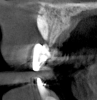

The intraoral examination revealed a substantial deficit of alveolar bone and gingival tissues in the maxillary right lateral incisor area. The ridge defect exhibited vertical and horizontal components, which were associated with a severe loss of clinical attachment on both the mesial aspect of tooth No. 6 and the distal aspect of tooth No. 8. Although probing depths were within normal limits, minimal keratinized gingiva was present and the soft tissues were acutely inflamed. Plaque removal was difficult because of the soft-tissue defect, gingival-margin location, and irregular soft-tissue architecture. Additionally, bone sequestration could be observed through the labial mucosa (Figure 2).

Tomographic images revealed a large tridimensional defect, with vertical and horizontal loss of bone extending to the apical third of teeth Nos. 6 and 8. Additionally, a buccal bone dehiscence was evident on tooth No. 5, and thin labial plates secondary to the orthodontic movement were present in several areas (Figure 3 and Figure 4).

Fig 2. A failed implant and bone-graft procedures had resulted in a substantial iatrogenic gingival-alveolar defect.

Figure 2

Fig 3. Tomographic images revealed a tridimensional defect extending to the apical third of teeth Nos. 6 and 8, a buccal bone dehiscence on tooth No. 5, and associated thin labial plates.

Figure 3